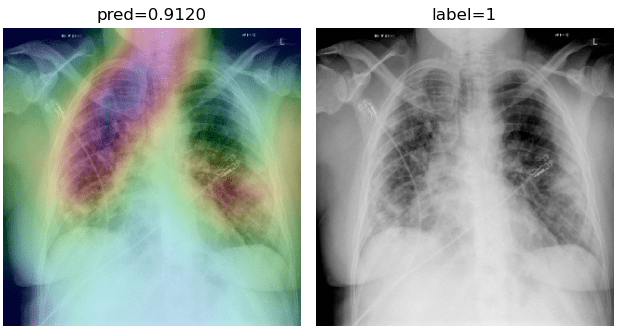

While text removal methods can prevent overfitting, we can simply force the model to look into the lungs in order to address both problems in one effort. To accomplish this task, a U-Net based segmentation illustrated in Fig. 4 is applied to the input images before enhancements. Visualization results for COVID-CXNet with the ROI-segmentation block are shown in Fig. 18.

Refer to caption

Figure 18: Grad-CAM visualization of the proposed model, trained with lung-segmented CXRs, over sample cases.

A figure with more Grad-CAMs is attached in Appendix B. From Fig. 18, it can be observed that COVID-CXNet with ROI-segmentation has delivered superior performance regarding the localization of pneumonia features. Worthwhile to mention that image augmentation is expanded by adding zoom-in, zoom-out, and brightness adjustment. Label smoothing is also applied to the loss function.

The proposed method has shown a negligible drop in metric scores; accuracy is decreased by 0.42%, and f-score is declined by 0.02. This decrease is a result of training with a larger dataset and accurately segmented ROIs, which means it has become more robust against unseen samples. There is a trade-off between catching good features and higher metric scores; while better features result in a more generalized model, high metric scores may indicate overfitting.